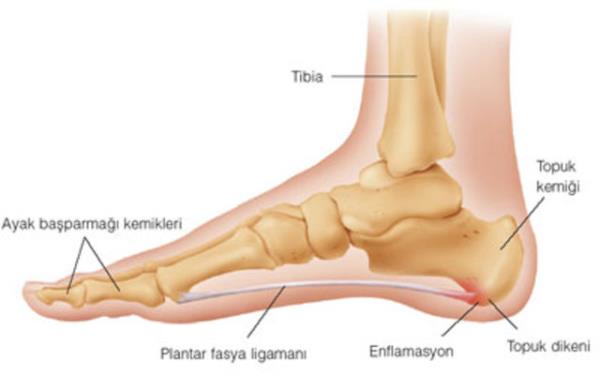

17. <br><b>Plantaris kası </b></br>  Plantaris kası hayvanlar tarafından, nesneleri ayakları ile tutmak ve kontrol etmek için kullanılır (maymunlar ayaklarını elleri kadar iyi bir şekilde kullanabilir).

Plantaris kası

Plantaris kası hayvanlar tarafından, nesneleri ayakları ile tutmak ve kontrol etmek için kullanılır (maymunlar ayaklarını elleri kadar iyi bir şekilde kullanabilir).

18. Bu kas insanlarda da aynı şekilde mevcuttur ancak o kadar az gelişmiştir ki vücudun diğer bölümlerinden herhangi birinin yeniden oluşturulmasında dokuya ihtiyaç olduğunda, doktorlar tarafından yerinden alınarak kullanılırlar.

Bu kas insanlarda da aynı şekilde mevcuttur ancak o kadar az gelişmiştir ki vücudun diğer bölümlerinden herhangi birinin yeniden oluşturulmasında dokuya ihtiyaç olduğunda, doktorlar tarafından yerinden alınarak kullanılırlar.

19. Bu kas insan vücudu için öylesine önemsizdir ki insanların %9'u bu kasa sahip olmadan doğarlar.

Bu kas insan vücudu için öylesine önemsizdir ki insanların %9'u bu kasa sahip olmadan doğarlar.